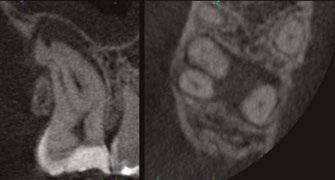

On a recent second molar case where I did not take a 3D scan prior to root canal treatment, the patient returned several days later still in pain! I took a scan and appreciated their deep split, forked in the last 5 mms of the distal canal (Figure 8). Without a CBCT scan, it’s easy to miss — I did! CBCT helps prevent this from happening by catching those variants and hard-to-find issues, which are not as rare as we think. This was another case that helped shape my current imaging protocol, so that now I scan nearly all of my patients. I honestly can’t imagine practicing without my CBCT unit — similar to when the microscope was introduced to endodontics.

Figure 7: Planned-for access with the scan info on this extremely calcified canine Figures 8 and 9: 8. Deep distal split with PARL. 9. Missed buccal canal; history of previous RCT, post, crown and apico Figure 10: Retreatment consultation. PA from GD Figure 11: Scan images show a previously existing strip perforation

what the literature suggests. And, when I know how many and where the canals are (Figure 13), I can take measurements on the scan and work more efficiently — measuring my working lengths of each canal, appreciating severe curves or calcifications, and knowing where canals can be expected to be located, again, rather than removing unnecessary tooth structure to find if it is there, or not!

As an endodontist, I often treat heavily restored teeth. I am often planning my accesses based on the scan’s information. This saves time and conserves more tooth structure. I’m not looking for canals that may or may not be there, and I’m looking for canals under the targeted/planned access — with the scan, I have an actual map (Figure 7)! CBCT directs me where to go and where to end. It reveals anomalies, which are more common than we think, so I can avoid iatrogenic incidents and provide less invasive treatments. Lower second molars with only two canals occur — often!

I’m also changing my treatment plans based on the data from my CBCT. Sometimes I look at a root canal treated PA and presume I know what I will do: a retreatment or an apico. Another recent, poignant case: a lower incisor with a previous RCT and a previous apico (Figure 9). Usually, once a tooth has had an apico, there may not be much left to offer and most of the time, the default is another apico, especially as there was very little room for an implant on the lower anteriors. I scanned the tooth and saw that a whole canal had been missed — twice! The RCT and the apico had left the buccal canal completely untouched. I changed my treatment plan based on this information!